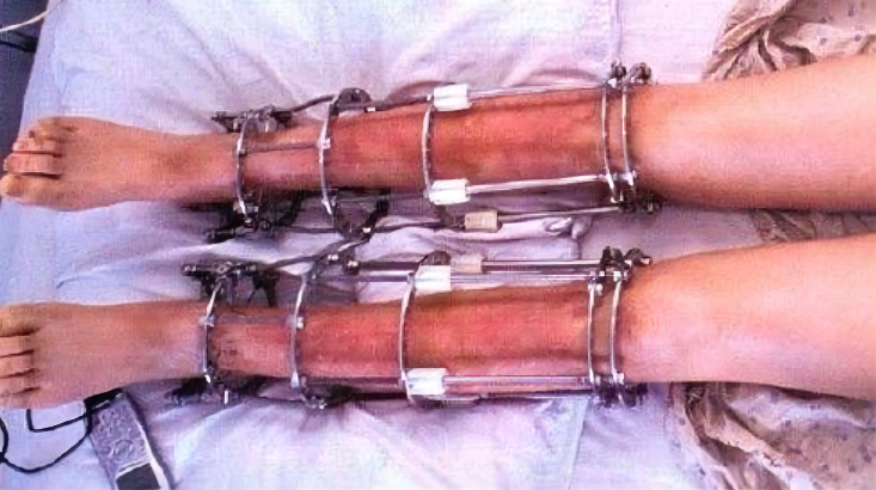

这是为天生残疾的需要延长肢体的病人研发出来的调节方法,对手术的实施要求也相当严格。

简单地说,这种手术会将人体的骨骺线再次打开,在里面植入一个固定器。

然后,通过人为地调大固定器之间的距离,刺激细胞和骨骼再生。当骨骼的生长使人达到理想的身高后,医生会再通过一次手术将人体内的固定器取出来。

虽然听起来简单,但是实际上,这种手术的风险极大。以外力方式强行拉长腿部的组织和细胞,稍有不慎就会酿成严重的后果,甚至致残。

李亚诺就是接受了这种增高手术,增高了7.2厘米。

当时,为他调节的医生告诉他,手术后的三个月要适当地运动;等待八至十二个月,他就可以如正常人一般行走了。

但是,手术的种种后遗症却逐渐缠上了他。

他遭遇了包括骨外翻、X型腿等在内的一系列问题。

而且,在日常生活的行动中,李亚诺的腿也不如以前那么灵活自如了。

可以说,为了增高这7.2厘米,他付出了巨大的代价。他本人也开始后悔当初的选择。

目前,国内已经明文禁止对躯体健康的人实施这种“断骨增高”手术。